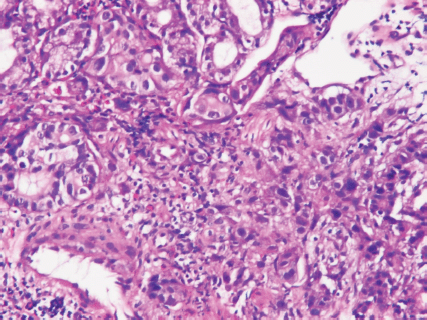

An upper gastrointestinal tract endoscopy led to the finding of a giant gastric ulcer over lesser curvature of the stomach (Figure 2). Pathology study of the biopsy specimen from the ulcer confirmed the nature of a poorly differentiated carcinoma (Figure 3) positive for cytokeratin AE1/AE3, with morphology patterns in favour of a gastric rather than a pancreatic origin. Immunohistochemical staining afterwards revealed only moderately positive expression of dihydropyrimidine dehydrogenase (DPD) (Rabbit monoclonal DPYD EPR8811: ab134922, Abcam, Cambridge, UK) (Figure 4) and totally negative expression of Bcl-2 (Clone bcl-2/100/D5, NovocastraTM HD, Leica Biosystems, UK) (Figure 5).

Figure 3. Poorly differentiated carcinoma of stomach, lesser curvature site, endoscopic biopsy (haematoxylin and eosin stain ×400).